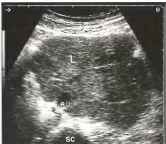

Рис. 33. Множественные мелкие парааортальные и брыжеечные лимфатические узлы (L) при болезни Ходжкина. VC - полая вена, АО - аорта, SC - позвоночник.

Изредка большие конгломераты лимфоузлов могут быть видны вокруг забрюшинных или мезентериальных сосудов и фактически «заковывают» их. В таких случаях обнаруженные лимфоузлы необходимо идентифицировать и измерять для оценки интенсивности их роста при последующих УЗИ.